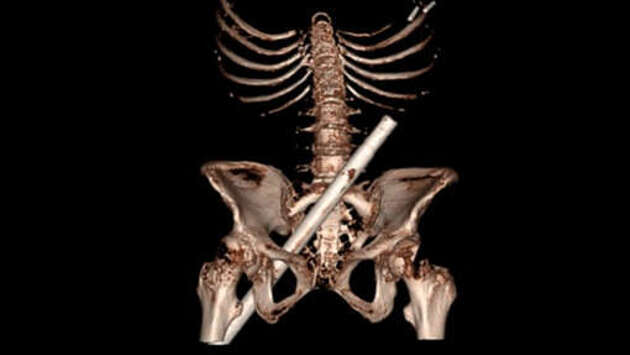

В Великобритании 54-летняя женщина была доставлена в отделение неотложной помощи Больницы Дейзи Хилл в Северной Ирландии – металлический стержень искусственной елки пронзил ее насквозь, пройдя через правую ягодицу. Об этом сообщают хирурги медучреждения в своей научной статье, опубликованной в журнале Clinical Case Report. Женщина упала на стержень со стремянки. Как только пациентку привезли в больницу, ей были сделаны рентген и КТ таза, однако перед этим пожарные полтора часа срезали остаток стержня, чтобы поместить женщину в аппарат. После обследования она была переведена в местный крупный травматологический центр. Однако из-за этого операция была проведена с задержкой. По словам медиков, несмотря на внушительную травму, угрожающего жизни кровотечения не было. "Весь персонал больницы был чрезвычайно добр и поддерживал меня, и я просто обязана им жизнью. Вся эта ситуация была очень тяжелой для меня и моей семьи", – отметила женщина.